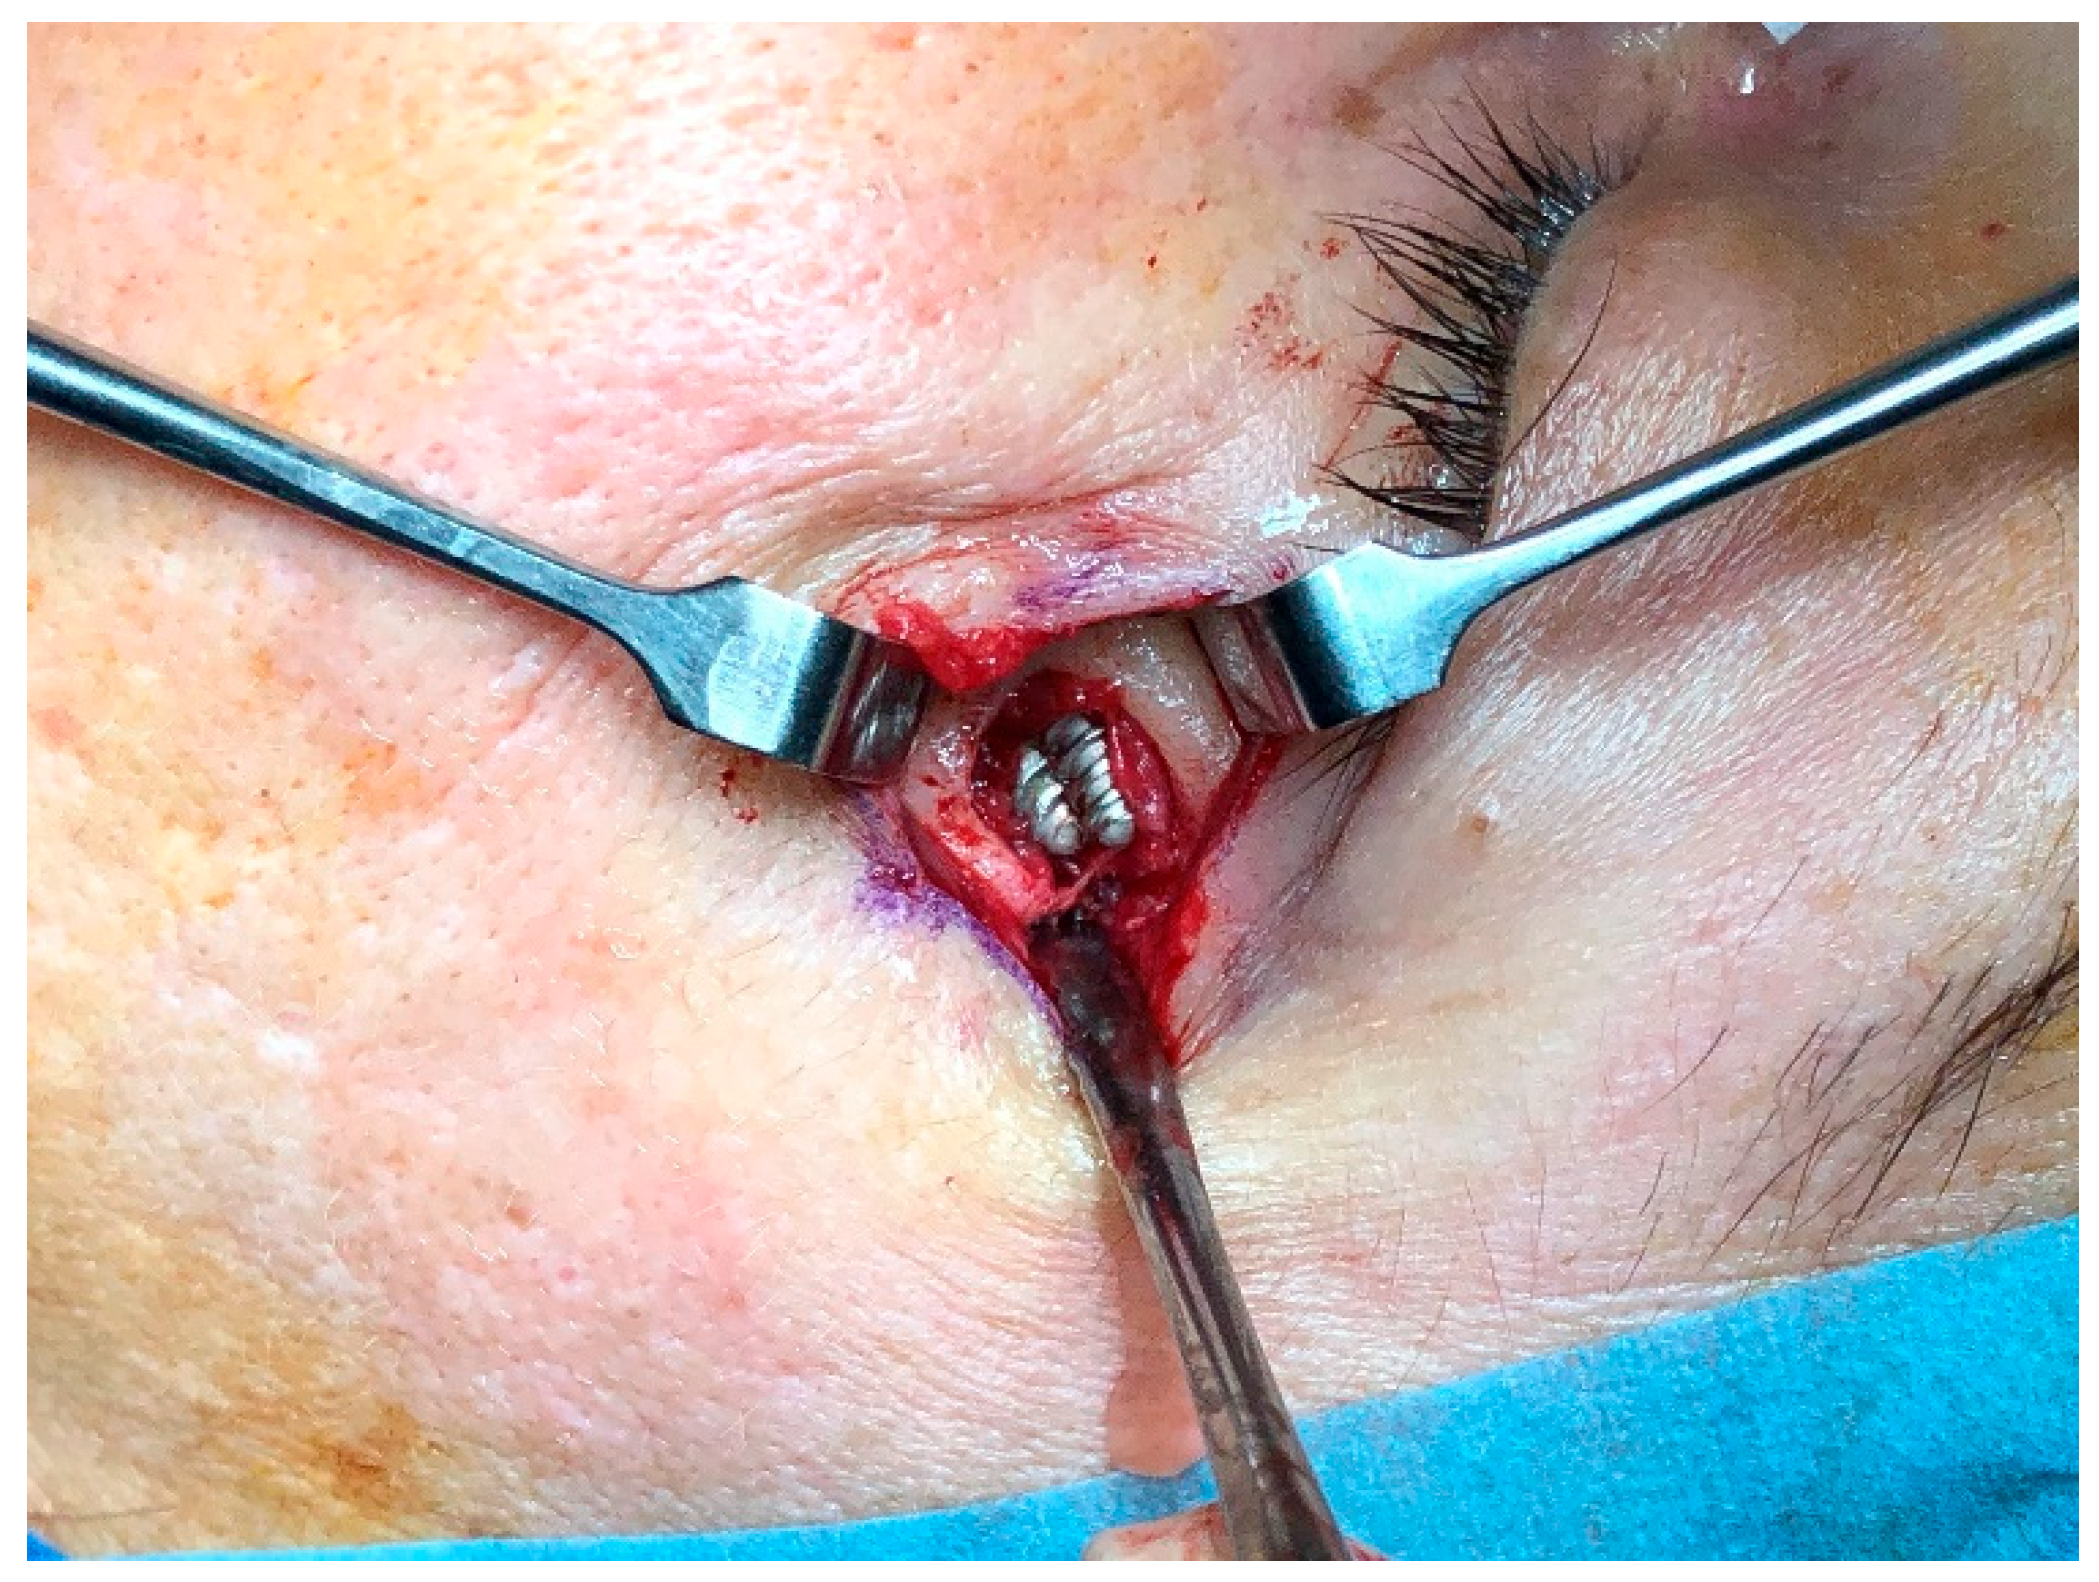

Figure 5.

After removing the skin fistula, a 10 mm diameter lack of bone area is shown. The etched parts are in close contact without inter-implant distance.

As the zygomatic bone around the ZIs was significantly reduced and the mechanical implant stability compromised, the authors preferred to remove it through oral approach (Figure 6). Bone curettage and a fistula repair were performed (Figure 7). The patient progressed well and was discharged on the first postoperative day. After follow-up, she was referred to her dentist for prosthetic rehabilitation.